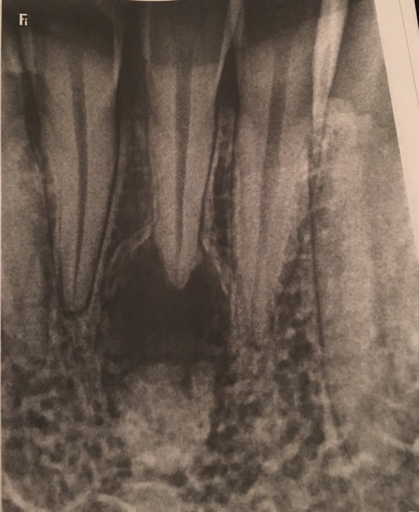

What are the chances of a tooth being rejected that has already received multiple restorations (over half is composite) after a root canal? I have an infection, and am receiving treatment. I have already taken one round of antibiotics, and start a second round tomorrow. I was told I could choose to do a root canal or extraction. I am trying to decide what would be in my best interest. The tooth in question has had multiple restorations, the most recent due to the tooth cracking and almost half of it falling out, therefor half composite. I have noticed that this tooth also moves slightly or is not as snug in the gums as the rest of my teeth. Since I have already spent $600-700 on this tooth my concern lies in spending the money for the canal and crown ... only to have it reject in a few months.

When a tooth has an infection, it tends to feel more mobile than your other teeth due to the inflammation and infections surrounding the tooth. Once the infection is under control and a root canal is completed, the ligaments surrounding the tooth with tighten back up. I can certainly understand your hesitation, however, most dentists' or Endodontists' will not perform a root canal if the tooth has a guarded prognosis. It will be imperative to have the crown placed immediately after the root canal in order to prevent any further fractures or trauma to the tooth. Always keep in mind, dental treatment is never guaranteed. The treatment is done with the best intentions, however you must responsible for your homecare and yearly dental x-rays in order to detect any recurrent or new dental caries. There is nothing better than your own teeth and extracting the tooth is a temporary fix, it must be restored with a dental implant or dental prosthesis such as a partial denture. Discuss your concerns with the treating dentist prior to starting treatment, in order to be sure you are making the best decision for your dental needs.